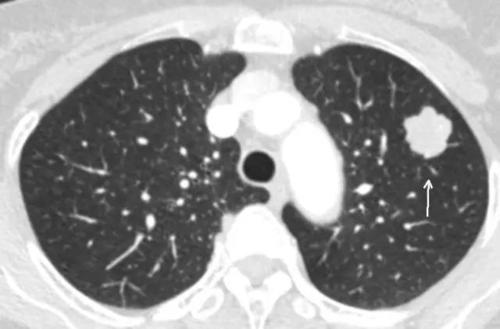

很多人在做体检的时候发现肺部有小结节,至于这个小结节的性质是什么样的,不做病理是不能明确的,而取病理是一个有创的检查,会对病人造成伤害,如果是肺癌的话,取病理还会造成肺癌的播散。再者,病理检查也不是百分之百的正确,它有一定的假阴性率。由于小结节并不会给患者本身带来任何的疼痛和不适,也不会在短时间内危及患者的健康和生命安全,所以这个时候问题不是很大。

为了观察肺部结节的性状,对于初次发现肺部结节的人就需要进行多次的复诊观察,如果结节一直没有长大,那就不用管他。如果结节随着时间的延长逐步的增大,并且性质发生变化,就需要手术处理。